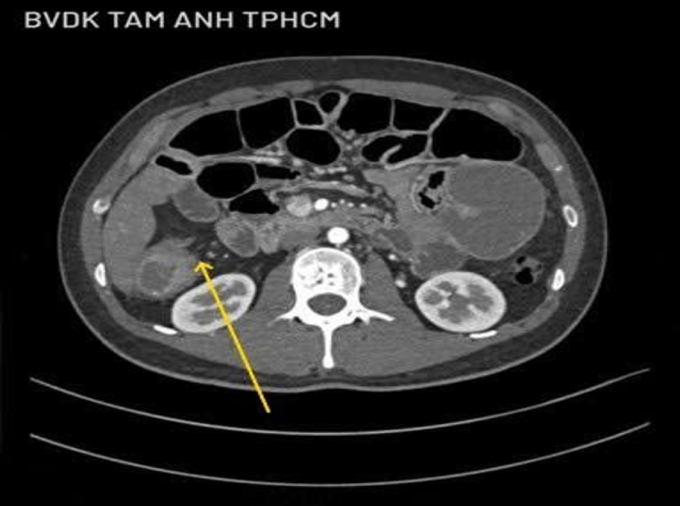

Anh Công ban đầu được chẩn đoán viêm dạ dày, ruột kích thích, điều trị bằng thuốc không đỡ, đến Phòng khám Đa khoa Tâm Anh Quận 7 chụp CT 100.000 lát cắt cho thấy đại tràng phải và các quai ruột giãn. Một đoạn ruột 5 cm mất cấu trúc, thâm nhiễm mỡ nhẹ xung quanh, nhiều hạch nhỏ xuất hiện quanh tổn thương. Ảnh nội soi cho thấy đại tràng góc gan có khối u sùi làm hẹp lòng, sinh thiết xác định ung thư đại tràng góc gan, tế bào ung thư xâm lấn sâu, rộng làm tắc ruột bệnh nhân.

Kết quả chụp CT 100.000 lát cắt cho thấy khối u lớn (mũi tên vàng) gần góc gan. Ảnh: Bệnh viện Đa khoa Tâm Anh